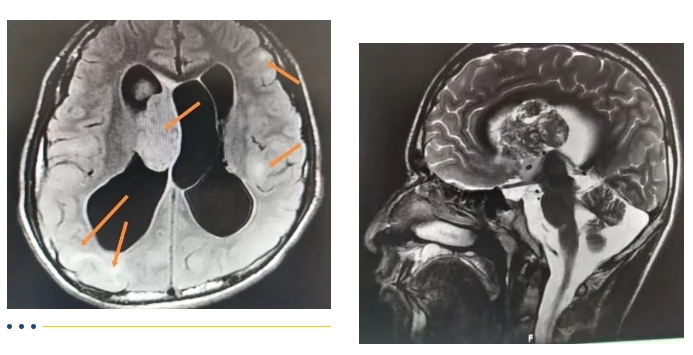

罕见病患儿四处求医无果,五院精准诊断即刻手术救治